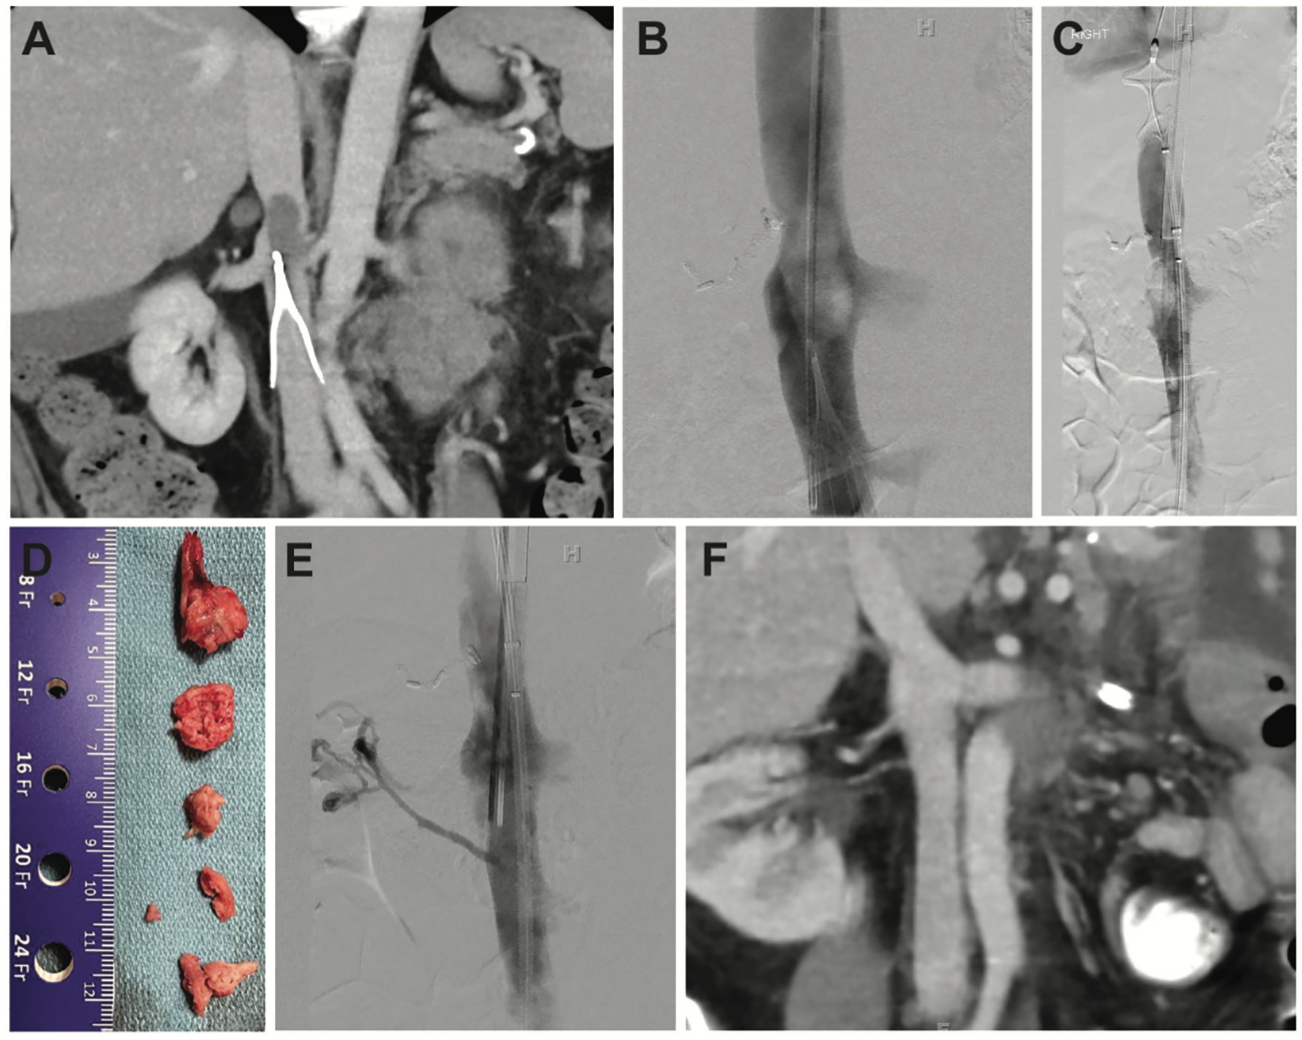

A 48-year-old female presented to the emergency department with fatigue and abdominal pain. Her hemoglobin was 6 g/dL and a computed tomography (CT) scan confirmed a recurrent gastrointestinal stromal tumor (GIST) with hemorrhage. A large thrombus was seen attached to the apex of an IVC filter (Figure 1A) which had been placed after a gastrointestinal resection surgery 2 years prior (Figure 1A). Due to embolization concerns, a complex intervention to retrieve the IVC filter safely and extirpate the residual IVC thrombus was undertaken. Given the bleeding risk, the patient did not receive anticoagulation.

The patient was positioned supine, and her right neck and bilateral inguinal regions were prepped. A focused ultrasound of the right neck was performed demonstrating that the right internal jugular (IJ) vein was patent and free of thrombus. Under direct sonographic visualization, the vessel was accessed with a micropuncture kit. An .035-inch guidewire was advanced into the IVC and the micropuncture sheath was exchanged for a 6 French (F) vascular sheath. A multi-side port infusion catheter was advanced and an inferior venacavogram showed a large filling defect corresponding to the prior CT finding (Figure 1B).

A focused ultrasound of the right inguinal region demonstrated that the right common femoral vein (CFV) was patent and free of thrombus. Under direct sonographic visualization, the right CFV was then accessed with a micropuncture kit, and an .035-inch wire was advanced centrally into the IVC. The micropuncture sheath was exchanged for a 12F vascular sheath that was advanced into the IVC with a radiopaque tip placed just above the IVC filter. An Inari FlowTriever catheter containing 3 self-expanding nitinol mesh discs (Figure 2B) was advanced through the sheath and the 2 most cephalad discs were deployed in the IVC above the level of the existing right IJ vein sheath tip, to provide embolic protection during filter retrieval (Figure 1C).

After thrombus aspiration, a 12F sheath was advanced through the existing 24F Intri sheath with the distal tip advanced to the level of the filter. A 15 mm EN Snare System (Merit Medical) and 6F catheter were inserted through the introducer. After multiple unsuccessful attempts to engage the filter hook, a guidewire was advanced centrally through the sheath to help redirect the snare and catheter. Subsequently, the snare was used to successfully engage the filter hook. The 12F sheath was advanced over the filter and the snare and filter removed as a single unit. The IVC filter was closely inspected, confirming that the IVC filter was intact and had been removed in its entirety. A large piece of chronic thrombus was aspirated through the sheath at the time of filter retrieval and no significant thrombus remained in the filter (Figure 1D).

Subsequently, the Inari ClotTriever System (Figure 2C-D) was advanced through the 24F Intri sheath, placed distal to the thrombus, and the nitinol coring element was expanded. With a single pass, additional chronic thrombus was successfully removed. A final inferior venacavogram demonstrated successful thrombus resolution (Figure 1E).

All wires and catheters were removed. The right CFV and IJ vein sheaths were removed, and hemostasis was achieved with manual compression and purse string suture, respectively. The patient was transferred to the postanesthesia care unit without postprocedure complications. A follow-up CT performed 2 weeks later confirmed thrombus clearance (Figure 1F).